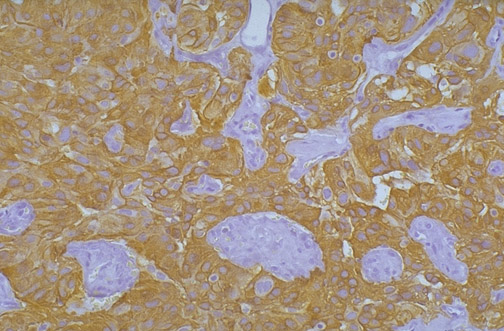

This ependymoma has positive staining for glial fibrillary acidic protein (GFAP) indicating it is of central nervous system origin.